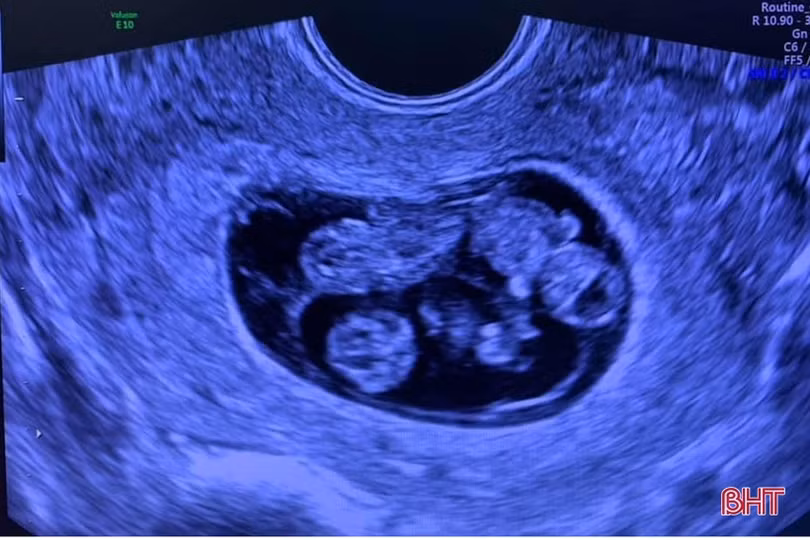

Nhớ về hành trình mang thai và sinh con của mình, chị Trương Thị Giang (SN 1989) và anh Nguyễn Gia Dương (SN 1988) vẫn không khỏi bồi hồi xúc động. Sau khi sinh đứa con trai đầu bằng phương pháp sinh mổ vào năm 2016 thì cuối năm 2018, chị Giang được bác sĩ chẩn đoán mang tam thai tự nhiên vô cùng hiếm gặp. Đó là tam thai chung bánh nhau, khác túi ối. Nghĩa là có 3 thai nằm trong 3 bọc ối khác biệt nhưng lại chung 1 bánh nhau, chung 1 đường nuôi máu.